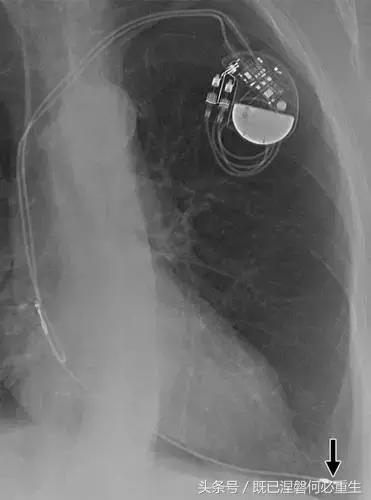

图5AB 在两个不同的患者电极错位和心室穿孔的例子。A,72岁的女性电极错误。 正位(A)和外侧(B)胸部X光片显示圣犹达医学双心室植入式心律转复除颤器与上腔静脉不适当的心房导线位置。 心房导联(箭头,A和B)的尖端高于右心房的水平,并且已经不适当地定位在上腔静脉中。 关注冠状窦引线(箭头B)的正常位置是在侧向投影中右心室(RV)引线的后方。